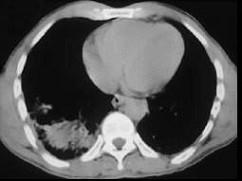

男,31岁,车祸后10小时余,请结合影像学检查,选出最可能的诊断 ( )A、矽肺B、大叶性肺炎C、肺结核D、气胸伴肺挫伤E、肺癌

问题 男,31岁,车祸后10小时余,请结合影像学检查,选出最可能的诊断 ( )

选项 A、矽肺 B、大叶性肺炎 C、肺结核 D、气胸伴肺挫伤 E、肺癌

答案 D